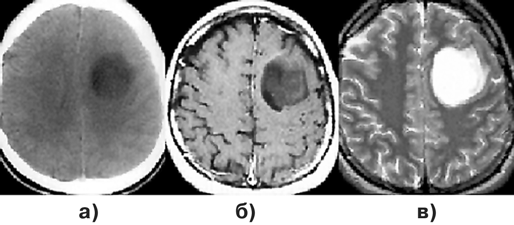

На КТ плотность опухоли весьма гетерогенна (рис. 4а). Центральная зона низкой плотности представляет некроз, выявляемый в 95% случаев. Границы опухоли нечеткие. Петрификаты встречаются редко. Часто определяются кровоизлияния различной давности. Опухоль обычно окружена зоной перифокального отека, распространяющегося в белом веществе больших полушарий. ГБ обычно активно накапливают контраст. Усиление после введения контрастного вещества выражено часто неоднородно, контрастирование имеет характерный вид кольца с неоднородным внутренним контуром. В ряде случаев ГБ отсутствует узловой компонент, и опухоль растет инфильтративно, широко поражая полушарие. Рентгенологически признаки повреждения ГЭБ (накопление контраста) при этом нередко отсутствуют, и контрастное усиление мало изменяет характеристику сигнала от опухоли.

МР-проявления ГБ в целом отражают патоморфологические изменения, демонстрируя значительную гетерогенность опухоли. На Т1-взвешенных томограммах выявляется плохо отграниченное объемное образование со смешанным (изогипоинтенсивным) сигналом, центральным некрозом, которому соответствует сниженный по отношению к опухолевой массе сигнал (рис. 3в, 4в). На Т2-взвешенных изображениях выявляются участки гипо-, изо-, гиперинтенсивного сигнала от стромы ГБ, зоны некроза, кист и кровоизлияний. Выраженный “масс-эффект” и распространенный отек белого вещества часто сопровождают и небольшие по размерам опухоли (рис. 4б). Границы опухоли сливаются с перифокальным отеком.

Рисунок 4. Глиобластома правой височно-теменной области, распространяющаяся на подкорковые узлы:

а — КТ с контрастным усилением; б — МРТ, Т2-взвешенные изображения; в — МРТ, Т1-взвешенные изображения, с контрастным усилением; г — каротидная АГ